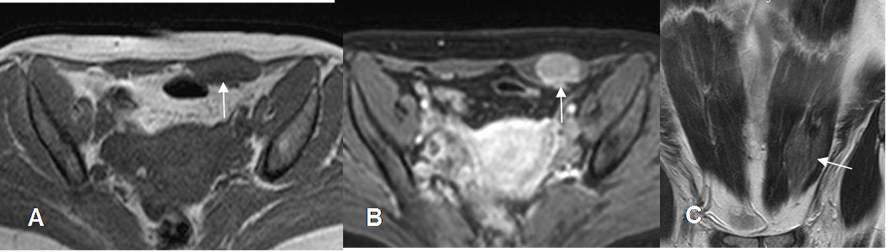

Fig 117. Tumor desmoide.

A: RM axial en T1, B: RM axial en STIR y C: RM coronal en T1 con contraste. Engrosamiento del músculo recto abdominal izquierdo, el cual es hipointenso en T1, hiperintenso en STIR y realza con el contraste, por tumor desmoide.

Fig 118.Tumor desmoide.

A: Rx AP. Efecto de masa periumbilical, que desplaza las asas intestinales.

B: TAC reconstrucción coronal y C: TAC axial. Gran lesión de consistencia sólida y heterogénea, que produce efecto de masa sobre los órganos abdominales, por tumor desmoide.